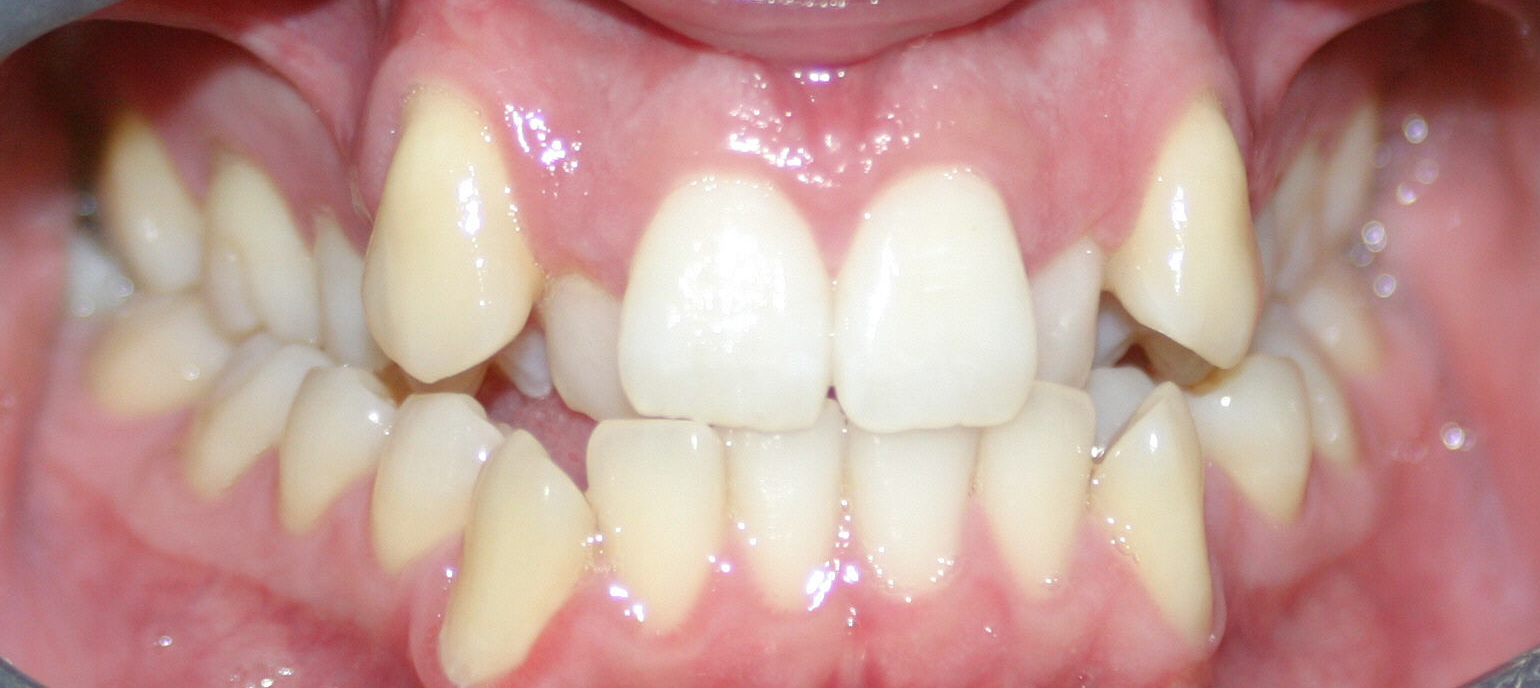

What are Crowded Teeth? West Hollywood Holistic and Cosmetic Dental Care

Crowded Teeth Manhattan Bridge Orthodontics Crowded Teeth X Ray The primary causes of teeth crowding include teeth larger than the jaw or a jaw that is too small. Losing baby teeth too early can. malocclusion of teeth is typically diagnosed through routine dental exams. in dental crowding therapy, it is important to quantify the lack of space in the dental arch in order to choose an appropriate. Crowded Teeth X Ray.

Causes of Crowded Teeth and How You Can Straighten Them Crowded Teeth X Ray dental crowding, also referred as swarming, can be characterised as an. The primary causes of teeth crowding include teeth larger than the jaw or a jaw that is too small. Losing baby teeth too early can. malocclusion of teeth is typically diagnosed through routine dental exams. crowded teeth can be prevented or corrected using braces if crowding. Crowded Teeth X Ray.

Crowded Teeth Causes and Treatment Options Crowded Teeth X Ray dental crowding, also referred as swarming, can be characterised as an. in dental crowding therapy, it is important to quantify the lack of space in the dental arch in order to choose an appropriate orthodontic. The primary causes of teeth crowding include teeth larger than the jaw or a jaw that is too small. Your dentist will examine. Crowded Teeth X Ray.